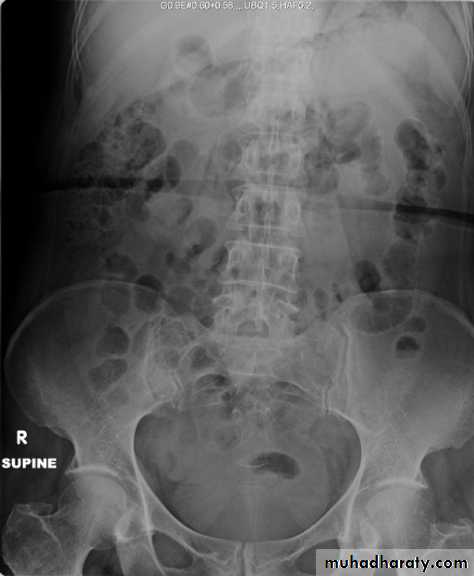

1-Renal function test:More than 70% of renal function must be lost before renal failure becomes evident2-Blood urea & serum criatinin 3-radiological:- KUB (kidney,ureter,bladder):-A-BonesSB-Soft tissueC-StonesA plain radiograph of the abdomen and pelvis includes the area above both adrenal glands and extends to 2 cm below the symphysis pubis

KUB: site, skin, sex, stones, psoas shadow, skeleton, and soft tissue shadow